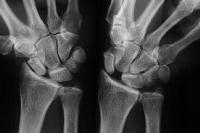

Preop

Click for larger image

Postop.